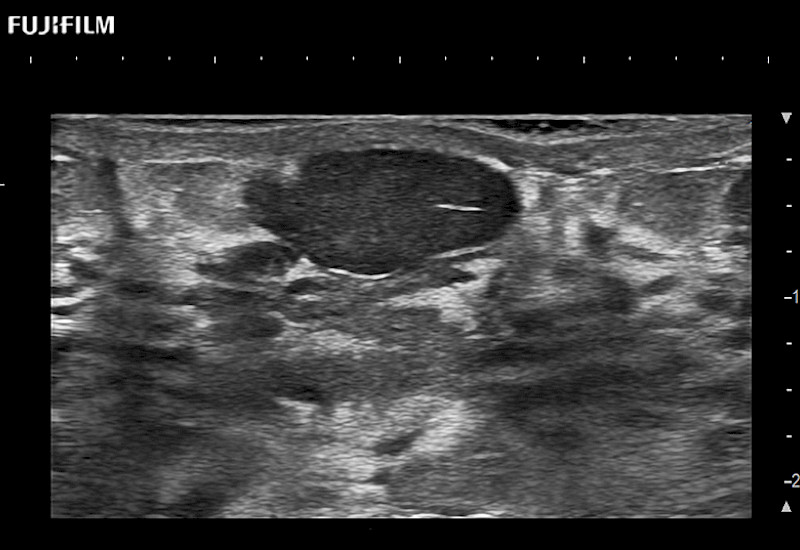

Fujifilm Healthcare understands that Surgical Oncologists demand excellence in their operating rooms — from their staff and the equipment they depend on. Fujifilm Healthcare's dedication to Surgical Oncologists provides outstanding ultrasound technology, professional support and the specialized tools necessary to best perform comprehensive real-time ultrasound imaging.

For precise surgical oncology ultrasound imaging, Fujifilm Healthcare offers premium level solutions that include:

for use during open and laparoscopic procedures: Tumor localization & staging, Ablation, Resection, Biopsy, Transplant, Abdominal exploration, Robotic surgery

Our dedication to Surgical Oncology allows us to offer superior image quality, outstanding system reliability and intuitive use of cutting edge technology.